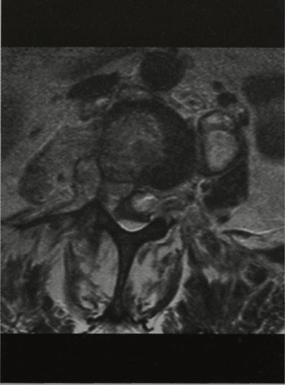

МРТ позвонка LIII (горизонтальная проекция, Т2-взвешенное изображение). Абсцесс распространяется через левое межпозвоночное отверстие в большую поясничную мышцу слева.

МРТ позвонка LIII (горизонтальная проекция, Т1 -взвешенное изображение с подавлением сигнала от жировой ткани и контрастированием). Псоас-абсцесс и эпидуральный абсцесс.